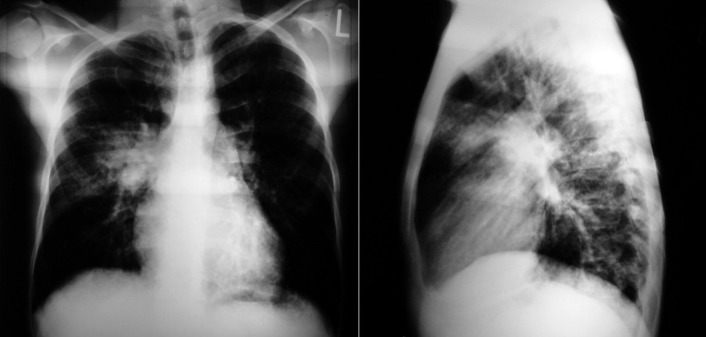

The radiographic findings of mitral stenosis ( Graphic 15-1 ; Figs. 15-1 to 15-16 ) reflect the pressure overload of the left atrium and pulmonary veins, and later of the right heart. As well, the commonly associated chronic atrial fibrillation contributes to (bi)atrial dilation. Associated rheumatic valvular lesions such as mitral regurgitation, tricuspid regurgitation, aortic insufficiency, and aortic stenosis/aortic insufficiency are common, and they alter the appearance of the heart.